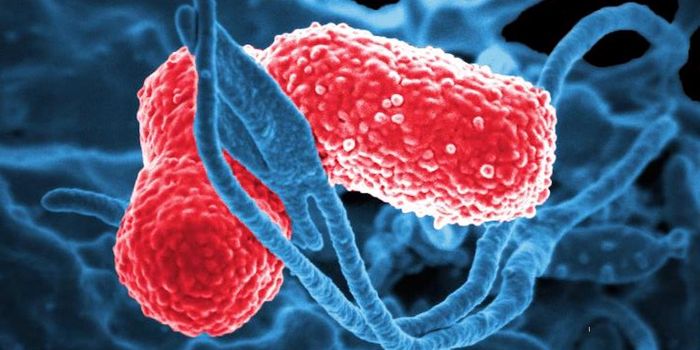

MAR 13, 2019Cell & Molecular BiologyAn ever-increasing number of bacteria are able to evade the effects of antibiotics, which is considered a serious threat ...

APR 03, 2018MicrobiologyAntibiotic resistance is a major public health concern. Around 23,000 Americans die of an antibiotic-resistant infection ...

NOV 25, 2019Drug Discovery & DevelopmentEvery year, around 700,000 people are estimated to die from drug-resistant infections thanks to our overuse of antibioti ...

MAR 16, 2015MicrobiologyTargeting deadly, drug-resistant bacteria poses a serious challenge to researchers looking for antibiotics that can kill ...

OCT 27, 2017MicrobiologyCarbapenem-resistant Enterobacteriaceae (CRE) are a group of bacteria that have high levels of resistance to specific an ...

SEP 19, 2016MicrobiologyBacteria that are resistant to drugs are an ever-increasing public health threat, with the Centers for Disease Control a ...

MAR 05, 2017MicrobiologyAlarm bells have been ringing all over the world about drug-resistant superbugs, which are expected to pose a huge threa ...

MAY 07, 2019MicrobiologyAntibiotic-resistant bacteria already cause the deaths of around 23,000 people every year, and that number is expected t ...